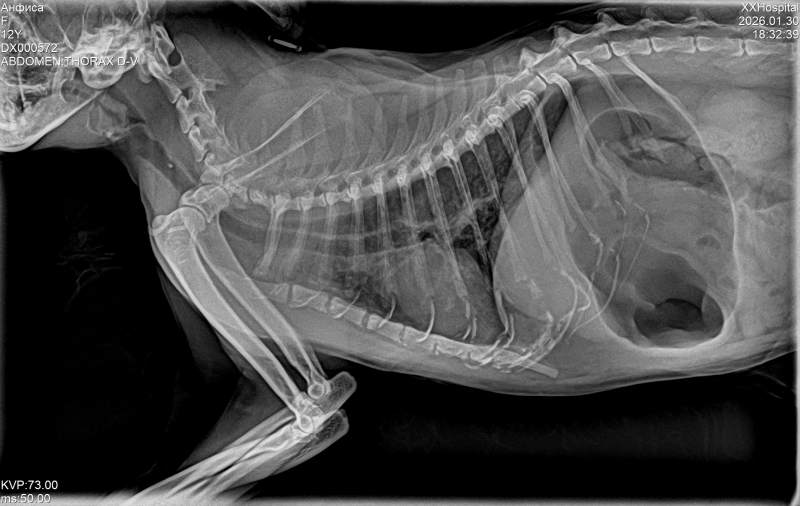

Посетили клинику доктора В.Г. Глушкова

Доктор Александр Олегович вел прием.

Главврач прокомментировал состояние легких по рентгену.

У кошки воспаление по анализу, давление тоже повысилось. По рентгену бронхопневмония, надо начинать снова панцеф. Есть скопление слизи. В ноябре уже было воспаление. Лечили. Рецидив.

Начинаем панцеф 10 дней. Продолжаем беродуал.

Также у кошки кальцинат в трахее. Это случайная находка.

На дыхание это не влияет, но трахея менее эластичная теперь.

По ОАК- воспалительный процесс. Также увеличен лимфоузел.

Контроль рентгена через 10 дней

Давление подскочило за 200, немного отдохнула- 170. все равно начинаем амплодипин снова. Нужно теперь мониторить давление- первые 3 дня потом раз в 3 дня.

Рентген 1900 ( в долг)- переделаем через 10 дней